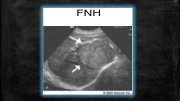

FNH